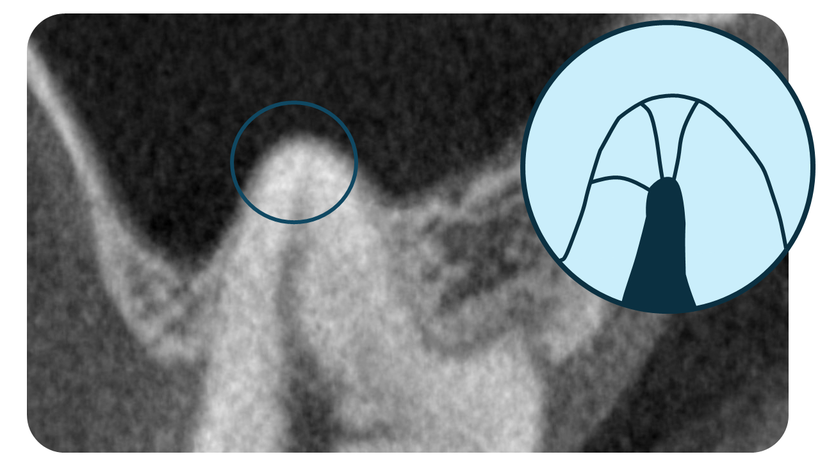

現代の根管治療ではCTスキャンの確認は必須といえます。

CT映像、精密モード65ミクロン単位の精度でレントゲンで見えないカット映像で根管の形態を確認。

根管治療の難症例では根管形態の確認のためCT撮影による3次元の詳細情報が必要です。

広範囲モードでは診断、矯正治療用に、高精度モードでは根管治療用に撮影します。